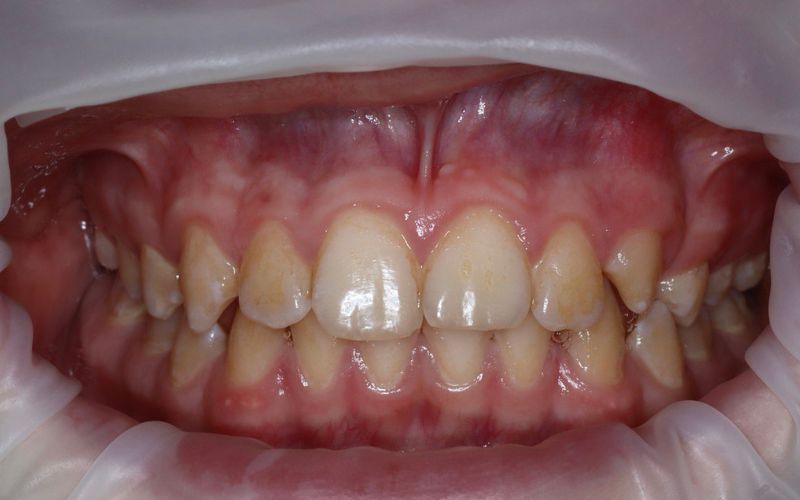

после

Мы провели профессиональную гигиену полости рта аппаратом Prophyflex и укрепление всех зубов фторирующим гелем с вишнёвым вкусом.

По окончании процедуры мы обсудили домашнюю гигиену, подобрали необходимые щётки и пасты и отработали технику чистки.